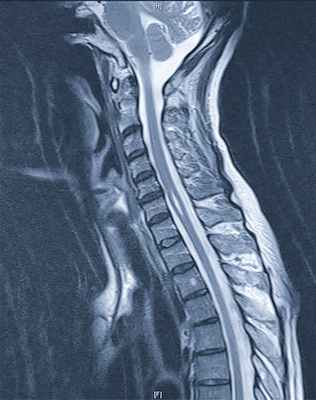

Магнито-резонансная томография (MRT) - диагноз сирингомиелия

Только при детальном обследовании можно обнаружить полости. Основой диагностики является, в первую очередь, история болезни и тщательное неврологическое обследование. При физическом осмотре врач проверяет рефлексы и обращает внимание на мышечную силу. Если в результате этих первоначальных шагов возникает подозрение на сирингомиелию, следует диагностика с помощью магнито-резонансной томографии (МРТ). На МРТ-снимках спинномозгового канала и прилегающих частей мозга можно увидеть полость и ее расширение. Чтобы увидеть циркуляцию мозговой жидкости, можно с помощью специального МРТ-исследования изобразить поток ликвора в виде фильма. При этом показывается пульсация мозговой жидкости в зависимости от сердцебиения пациента. Точная интерпретация этого исследования позволяет во многих случаях обнаруживать мельчайшие склеивания с нарушениями циркуляции мозговой жидкости.

МРТ спинного и головного мозга с контрастным усилением гадолинием

Подозревать наличие сирингомиелической кисты следует при развитии необъяснимого центрального спинального синдрома или другого характерного неврологического дефицита, в особенности нарушения болевой и температурной чувствительности по типу «капюшона».

Выполняется МРТ всего спинного мозга и головного мозга. Контрастное усиление необходимо для выявления сопутствующего опухолевого процесса.

Диагностика выполняется с помощью МРТ с контрастным усилением с использованием гадолиния.